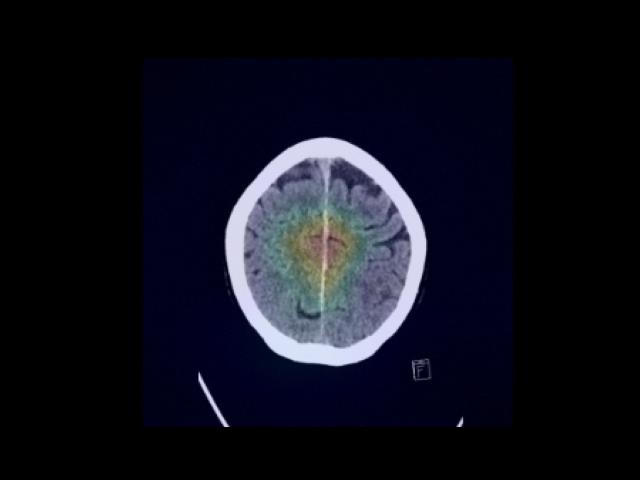

Sample Gallery